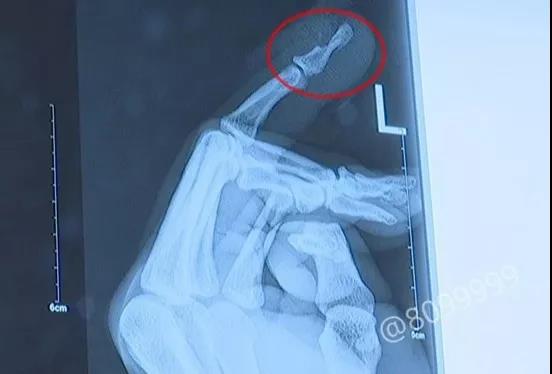

跟王师傅一起过来的一名工友表示,自己身上也没带钱,王师傅急诊挂号、入院预付的2000多块钱,都是由王师傅的妻子支付的。经过伤口探查、拍片检查,医生发现王师傅的手指伤的还不轻。

对于医生而言,这类手术或许只是常规的手术,但对王师傅而言,这样的意外受伤,却可能带来治疗费用的纠纷、与用工方之间可能出现的矛盾、以及影响后续工作等等问题。

▲王师傅手指受伤情况